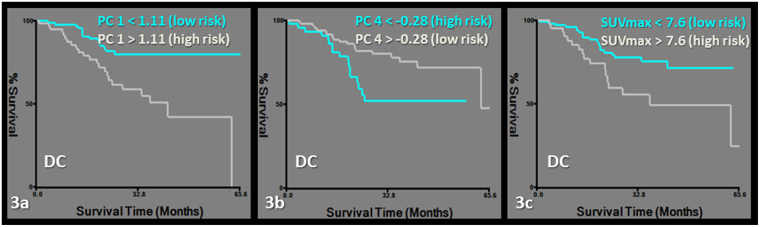

RFP was predicted by a model including PC1 and female predominance in gender. Features grouped together in PC1 were PET-derived first order features and CT-derived second order features (Tables 2, 3, 4, Fig. 2). DC was predicted by a model including PC4 and PC1 (Tables 2, 3, 4, Fig. 3).

Figure 3.

Kaplan-Meier survival curves for distant control (DC). Subgroups of low and high risk were determined by a cut-off value of 1.11 for PC1 (logrank chi-square: 11.62, p = 0.0006) (a), −0.28 for PC4 (logrank chi-square: 6.27, p = 0.01) (b) and 7.6 for SUVmax (logrank chi-square: 6.22, p = 0.01).

Finally, the added value of radiomics analysis in staging PET/CT was tested by rerunning the clinical outcome/survival analysis after entering SUVmax with the principal components, age, female predominance in gender, histology, stage and radiation dose. PC1 lost its predictive value over SUVmax for the models of RFP and DC. Female gender remained predictive of RFP and PC4 remained predictive of DC independent of SUVmax in the models (Table 2, Figs 2 and 3).